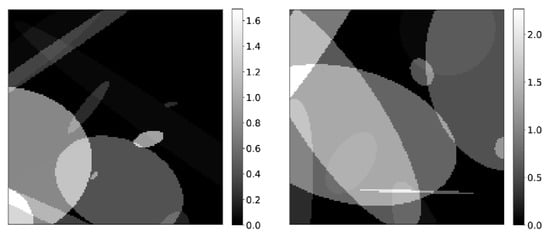

2.3.1. Synthetic Data Training

3.1. Results on Synthetic Data